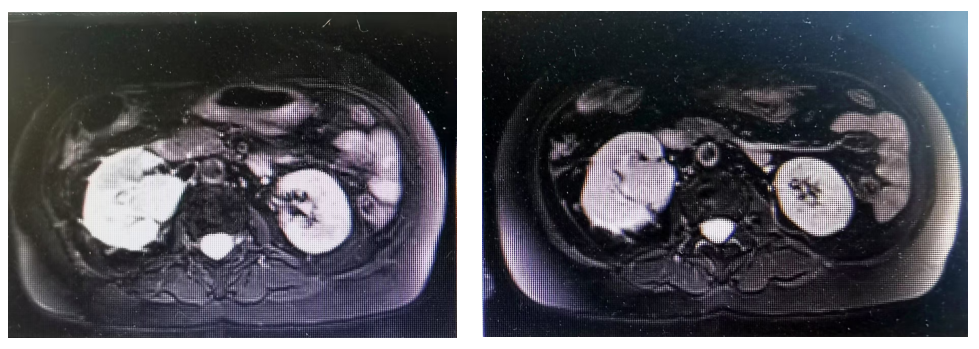

Key Imaging Examination: Enlarged right kidney, with a mass-like soft tissue signal in the right renal pelvis, showing mild progressive enhancement, approximately 3.2X4.4cm in size. An irregular patchy T2 signal is seen in the adjacent right upper back, with uneven mild progressive enhancement in the adjacent cortex, and irregular large areas of reduced enhancement inside. Fine vascular shadows are seen at the lower pole of the right kidney, with an irregular margin, and no obvious dilation of the right renal calyx. The left kidney shows no significant abnormalities in shape or signal, with no obvious dilation of the left renal pelvis or calyx, and no significant enlarged lymph nodes in the abdominal cavity or retroperitoneum, with no abdominal effusion.